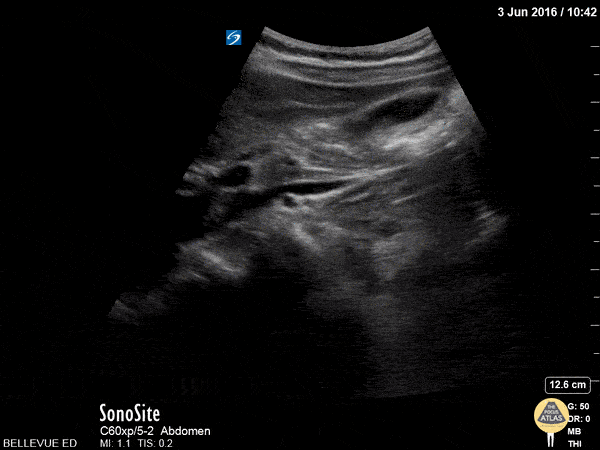

Biliary - Gallbladder Long Axis

In this clip we see the liver on the left of the screen, and in the center right a large anechoic ovoid structure which is the gallbladder. The gallbladder in long axis together with the portal triad in cross-section form the “exclamation point sign”. Hannah Kopinksi and Dr. Lindsay Davis - NYU Emergency Medicine